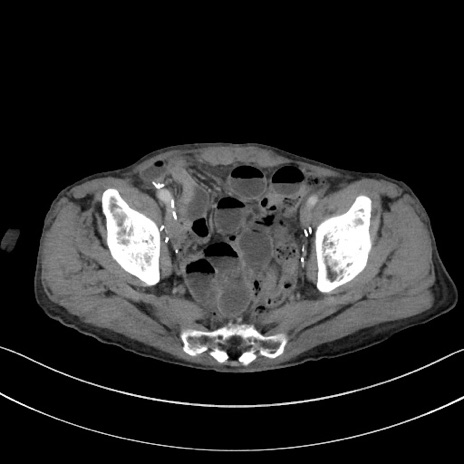

症例3(横断像)

【症例】 70歳代男性

【主訴】右鼠径部腫瘤、疼痛

【現病歴】本日朝より上記主訴あり、受診。

【既往歴】膀胱癌にて膀胱全摘、両側尿管皮膚瘻

【データ】WBC 5600、CRP 0.56